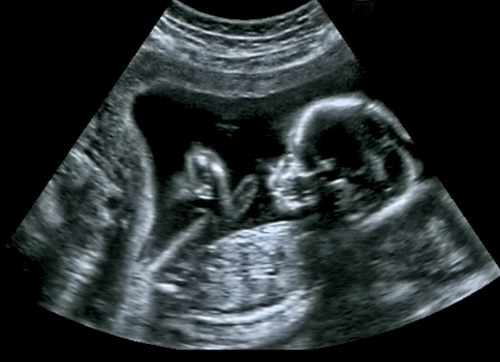

9)'Bebeğin Burun Kemiği Down Sendromu Olmadığını Gösterir'

gebelikle ilgili doğru bilinen yanlışlar

Burun kemiği gelişen bebeğin asla Down Sendromu olmadığını söylemek kadar, burun kemiği gelişmeyen bebeğin Down Sendromu olduğu kanısına varmak da yanlıştır.